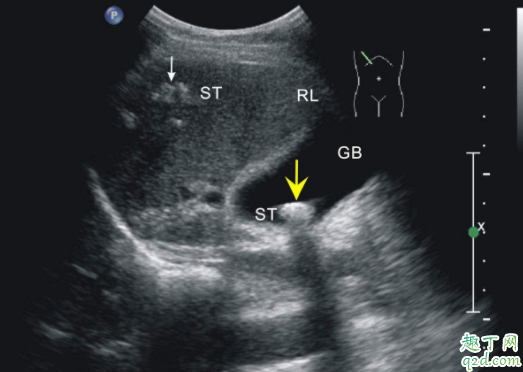

羊水的多少,一般用B型超聲診斷法,一啊不能妊娠期28-40周,最大羊水池徑線穩(wěn)定在5.1±2.1cm的范圍。AFD≤2cm則為羊水過少,≤1cm為嚴重羊水過少。